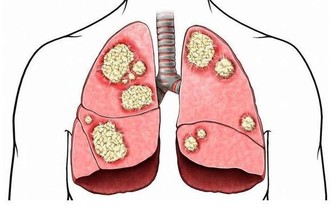

現在的醫療發展已經可以治療相當多的疾病,也儘管還有許多疾病無法治愈,但可以依靠藥物和其他治療方法延緩進展。不過,這些療法和治療效果有一個共同特點:越早診斷和開始治療效果越好,所以體檢發現的疾病萌芽,往往可以在發病初期被治愈或者控制,哪怕是癌症。等到了有症狀再去看醫生,很多疾病實際上已經進入末期了。